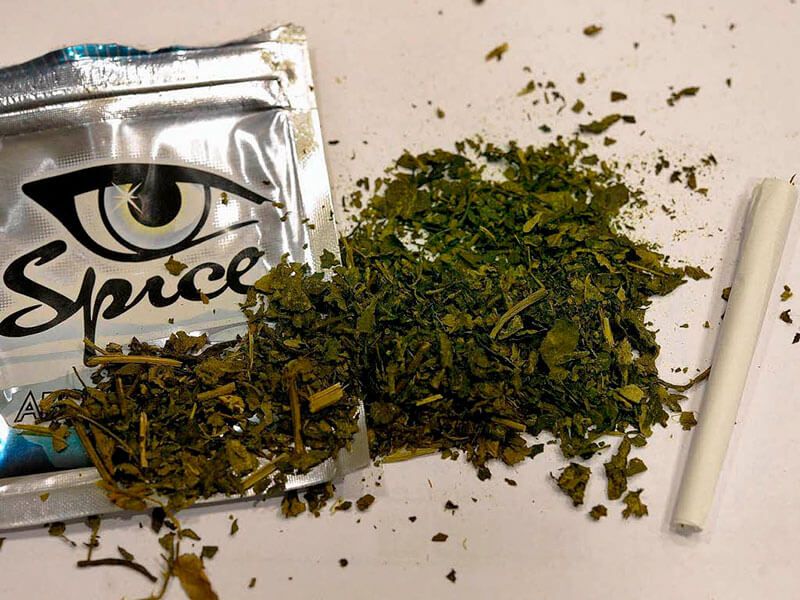

Это смесь для курения с химической обработкой. Относится к группе сильнодействующих наркотиков каннабиноидной группы. Точный состав смеси неизвестен, так как постоянно меняется.

Это смесь для курения с химической обработкой. Относится к группе сильнодействующих наркотиков каннабиноидной группы. Точный состав смеси неизвестен, так как постоянно меняется.

Спайс не просто наносит вред здоровью, но и может стать причиной преждевременной смерти. Оказывает сильное влияние на центральную нервную систему человека, как и соли, провоцирует различные психические нарушения.

Действие похоже на марихуану, но наркотик относят к категории синтетических, так как при производстве обрабатывается психоактивными химическими веществами.